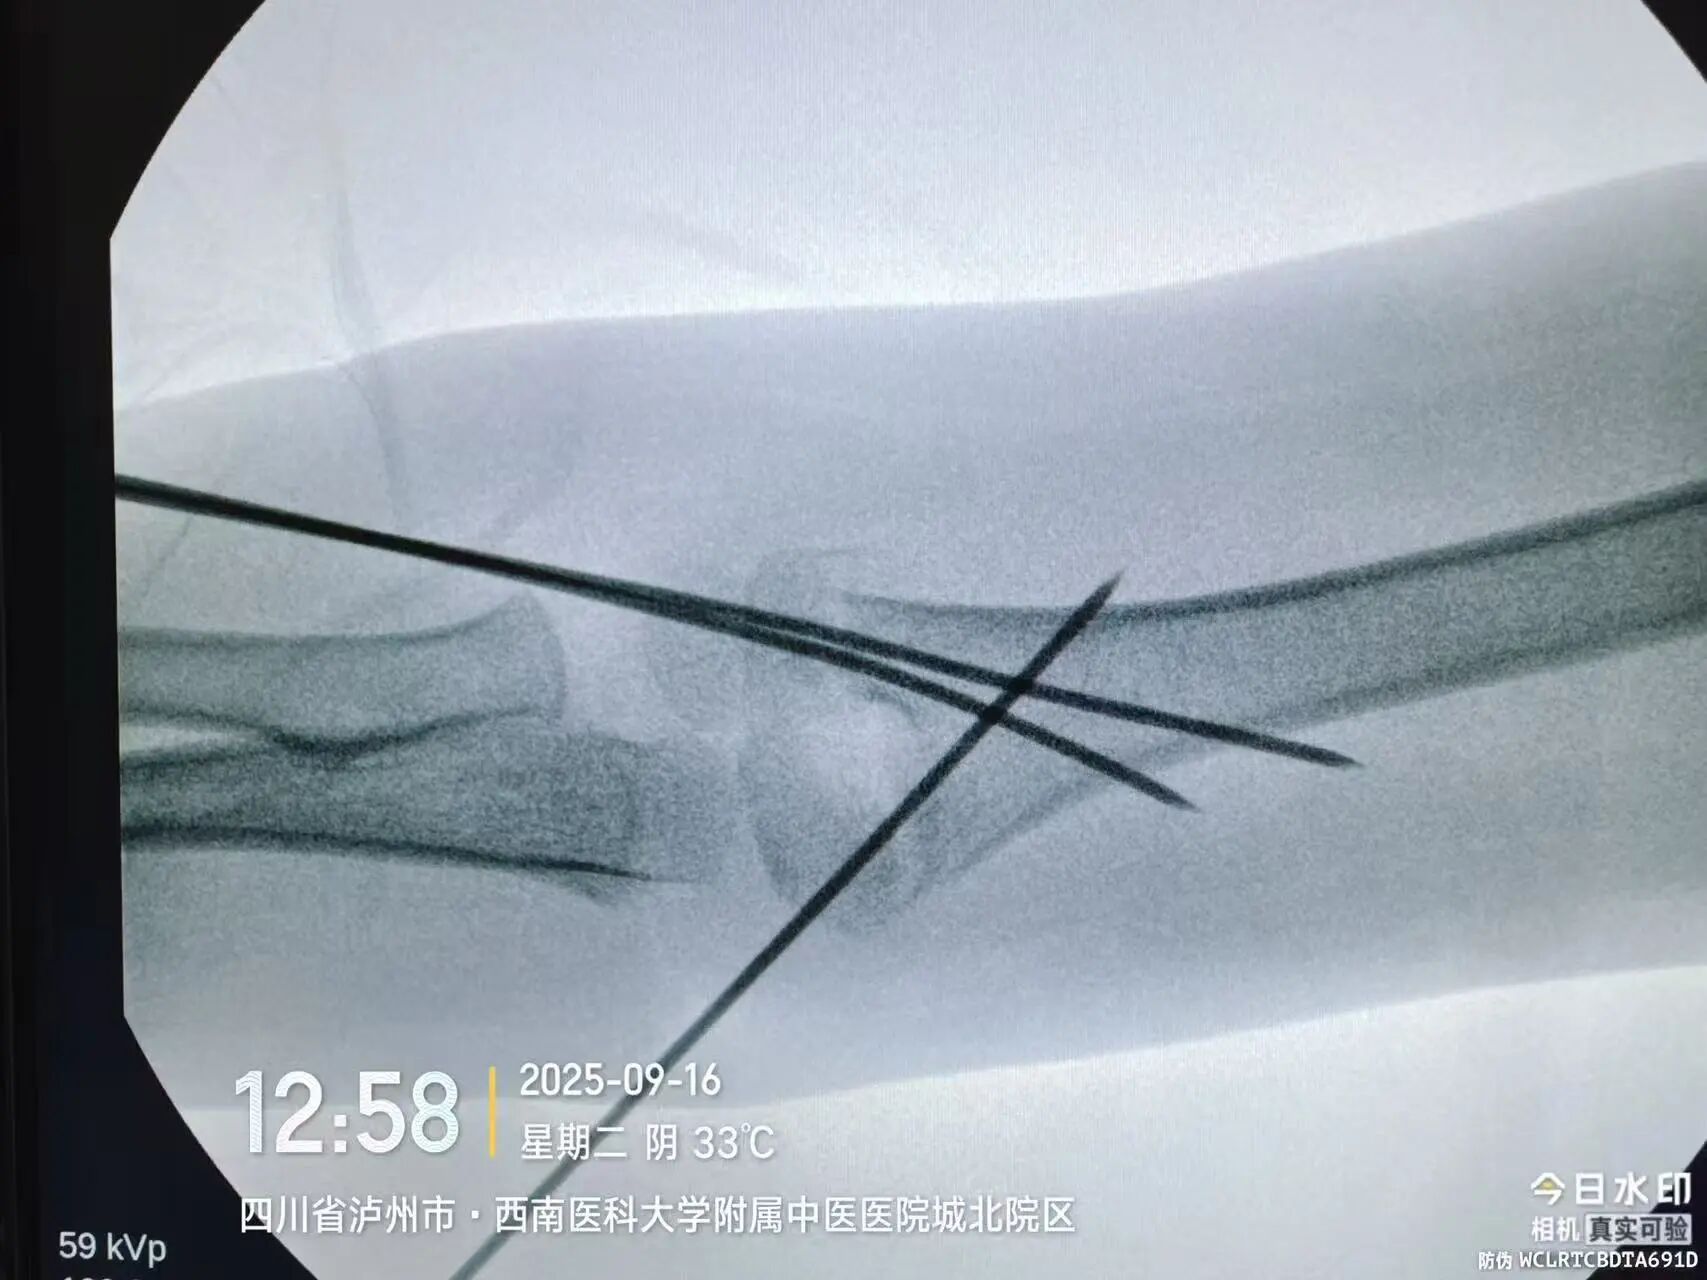

“孩子现在是最重要的初二,落下一周课就跟不上了!”小廖妈妈刚带孩子入院时,最焦虑的就是学习问题。让她意外的是,医院骨伤科手外·儿骨·烧伤整形组团队当即开通“儿童骨折急诊绿色通道”,仅用18小时就完成了术前检查、评估和桡骨远端骨折闭合复位经皮固定术。

同样“抢时间”的还有小罗和小周的治疗:4岁小罗9月15日深夜入院,10小时后顺利手术;7岁小周同一晚受伤,也在10小时内完成肱骨髁上骨折闭合复位经皮固定术。6岁小郑更是创下“4小时极速手术”纪录——早晨7点40分受伤,8点多入院,11点多手术结束,当天下午就能躺上网课。

“我们的目标是‘24小时内完成急诊手术’,尽量让孩子少耽误一节课。”骨伤科手外·儿骨·烧伤整形组主任陈孝均教授介绍,为了实现这个目标,团队制定了专属流程:孩子入院后,急诊优先开具检查单,放射影像科快速出片;骨科医生同步评估病情,确定手术方案;麻醉科提前做好准备,只要术前检查合格,立刻安排手术——哪怕是深夜或周末,团队也随时待命。